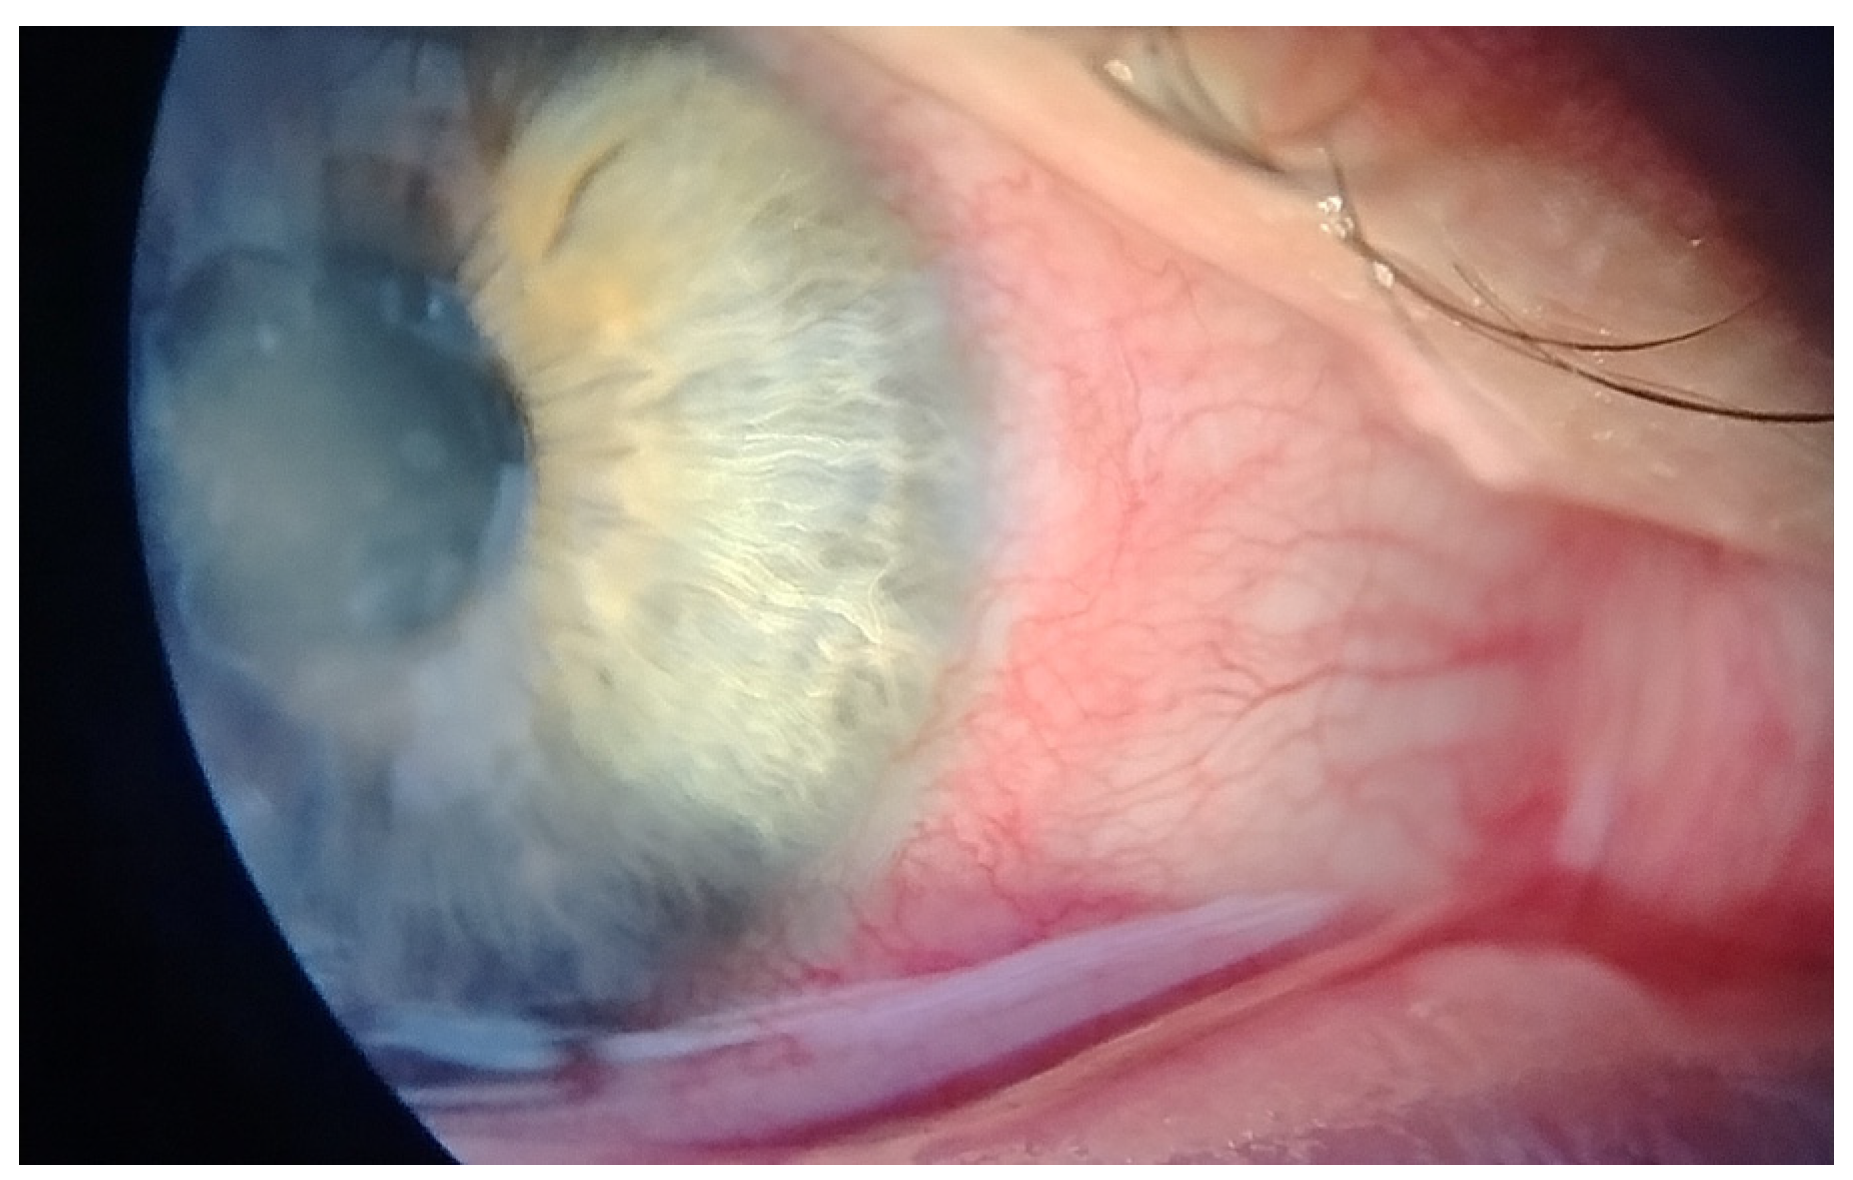

This case report describes a 35-year-old female who presented with redness, pain, tearing, photophobia, and vision loss in her right eye, beginning in mid-September 2024. The patient was a soft contact lens wearer due to myopia of −6.00 DS and reported showering and occasionally sleeping while wearing her contact lenses. She was initially treated for five days with topical corticosteroids and antibiotics by her primary care doctor, with no improvement, after which she was referred to an ophthalmologist. At her initial presentation in October 2024 at the University Hospital Centre Zagreb, the best-corrected visual acuity (BCVA) of the right eye was 0.4 logMAR. Slit-lamp examination revealed pronounced perilimbal injection (Figure 1), two fluorescein-negative stromal infiltrates at the 4 and 8 o’clock positions, and diffusely reduced corneal transparency with a centrally located ring-shaped infiltrate (Figure 2). Perineural infiltrates were also observed (Figure 3).

Figure 1. Perilimbal injection.